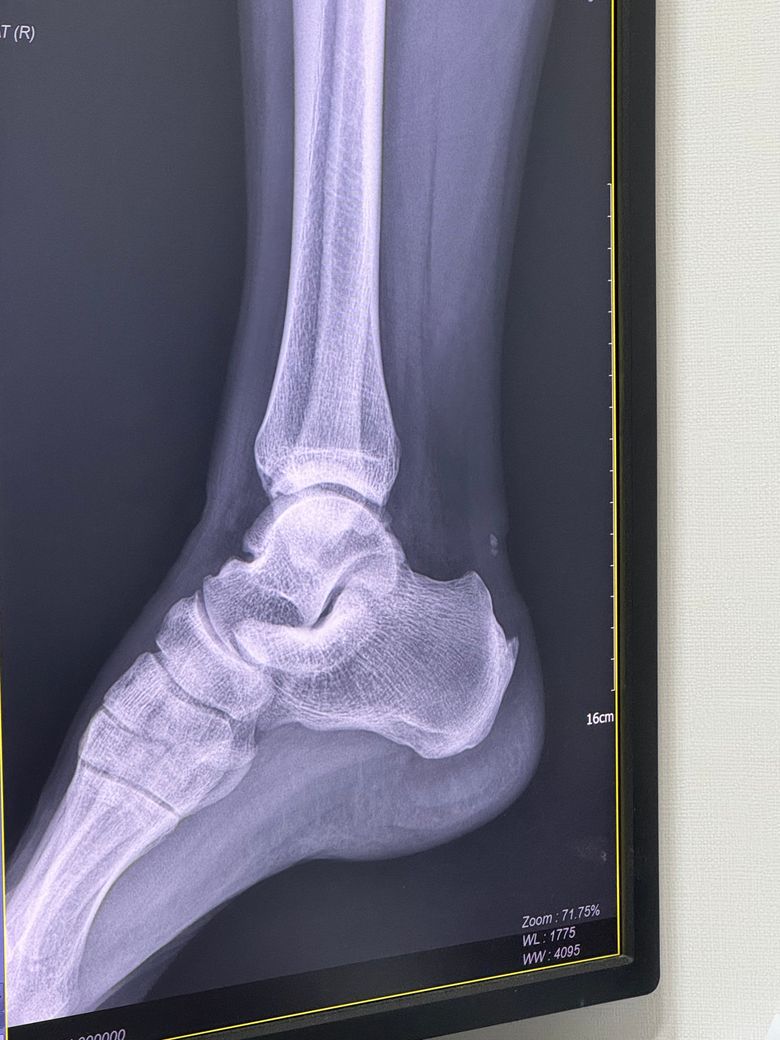

아킬레스 부착부에 일부 파열 및 하글런드 있다는 소견을 들었는데요

• 2번 째 사진